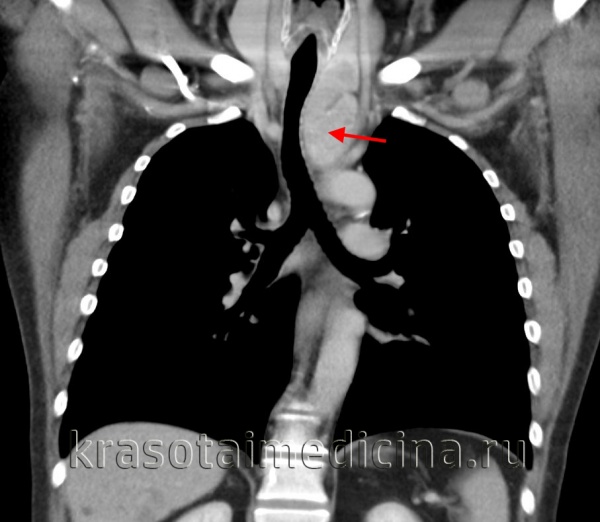

(б) Пациент со зрелой тератомой. При КТ с контрастным усилением на реконструкции в коронарной плоскости в преваскулярном отделе средостения визуализируется многокамерное кистозное объемное образование, содержащее небольшое макроскопическое включение жира. КТ является оптимальным методом для оценки протяженности поражения.

о Крупное мягкотканное объемное образование с дольчатым контуром в преваскулярном отделе средостения, умеренно накапливающее контрастное вещество

о Редко выявляются кистозные полости или кальцификаты

о Объемное воздействие на прилежащие структуры средостения

о Лимфаденопатия средостения

• КТ с контрастным усилением:

о Крупное мягкотканное объемное образование с дольчатым контуром в преваскулярном отделе средостения, умеренно накапливающее контрастное вещество; редко выявляются кистозные полости или кальцификаты

о Объемное воздействие на прилежащие структуры средостения о Лимфаденопатия средостения